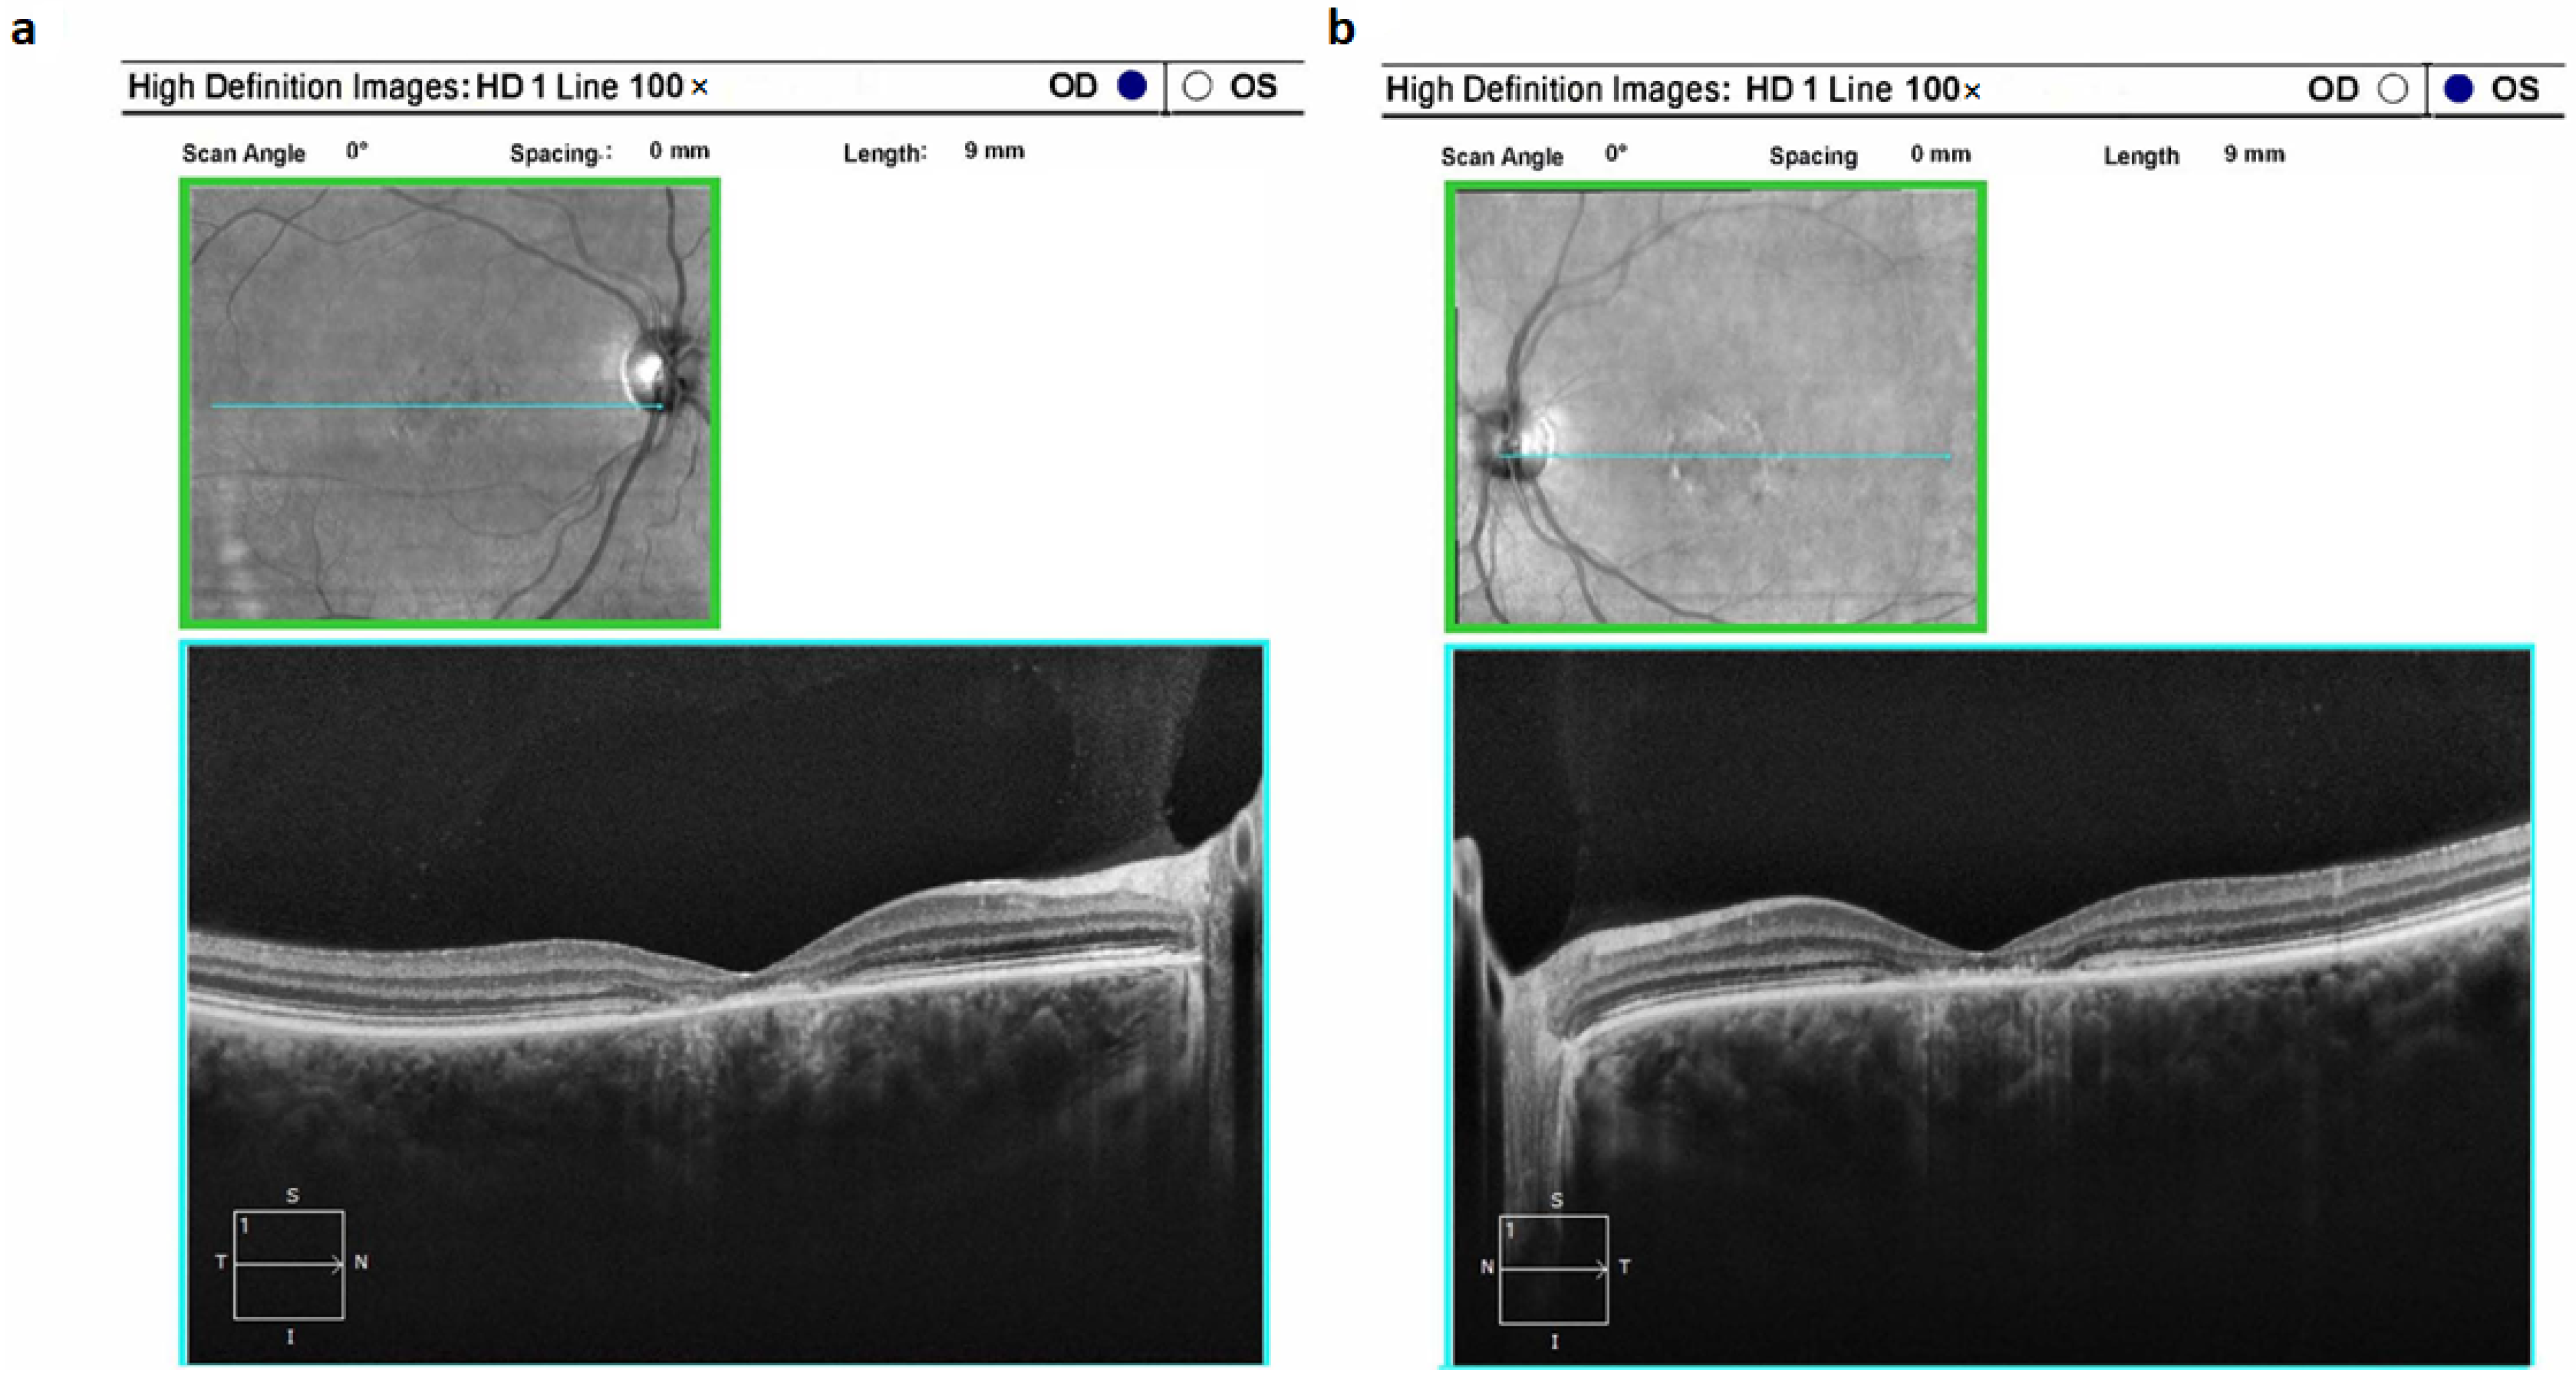

Retinitis pigmentosa type 19 (RP19) was identified in five cases, accounting for 4.17% of the total (5 out of 96). In all cases of RP19, a distinct pattern emerged that was characterized by a comprehensive atrophic alteration of the retinal pigment epithelium (RPE), juxtaposed with a relatively conserved macular region structure (Figure 3a,b). Among patients aged above 20 years, involvement of the photoreceptor layer within the pathological process was evident; however, this layer could still be discerned. Across all individuals affected by this condition, central vision demonstrated a prolonged preservation phase, even in the presence of a pronounced constriction of peripheral visual fields. Moderate pigment deposition, specifically of the “bone bodies” type, was notable on fundus examination (Figure 3c,d). It’s important to highlight that the optic disc, within this clinical subtype, exhibited partial indications of an atrophic process.

Figure 3. Optical coherence tomograms and image of the fundus of the right (a,c) and left (b,d) eyes of a patient (ID-76) with Retinitis pigmentosa 19 (RP19).